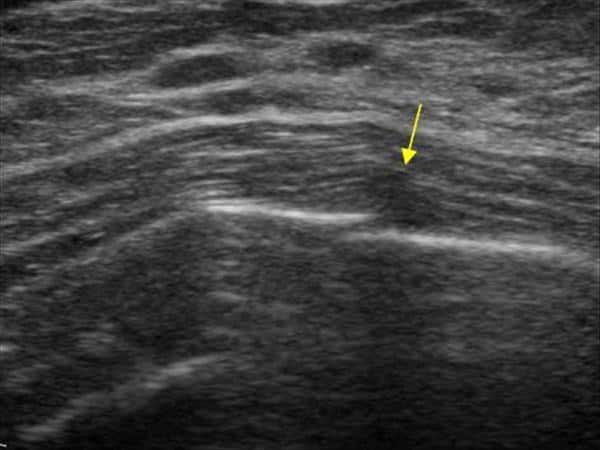

Gãy xương sườn

» Thông tin: Nữ giới – 52 tuổi.

» Lâm sàng: Chấn thương ngực.